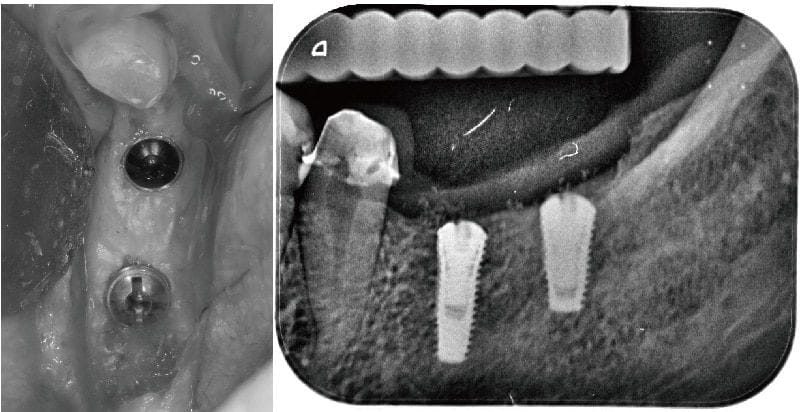

為 Miss Sung 拆除舊假牙換上臨時假牙與拔除殘根後,再安排進行 舒眠植牙 手術。過程中我們很順利的置放兩支人工牙根,手術的過程會比較舒適,術後恢復也順利良好。

圖示:舒眠植牙手術過程,順利植入兩支人工牙根

因為 Miss Sung 在這個區域缺牙多年,缺牙產生牙齦萎縮、角化牙齦不足等後遺症。

我在 牙周整形手術 服務頁中有說明若植牙假牙旁邊缺乏角化牙齦,會造成牙菌斑堆積或是局部發炎等問題,因此我們在植牙第二階段執行『游離牙齦移植手術』來增加她的植牙牙肉寬度,這樣牙齦能對以後的植牙假牙起到保護作用,利用牙刷清潔時會比較舒適,才能維持植牙長期的穩定性。

左圖為植牙手術後大約三個月,此時植體還在牙肉底下,照片中紅線區顯示角化牙齦不夠,通常至少寬度要 4mm 以上。

右圖為植體露出換上癒合帽,同時把牙齦補寬,補肉手術增寬牙肉後大約 6-8 週,我們利用數位牙科的技術與特殊植牙的口內掃描套件,就可以有效率且精準地把植牙假牙完成。